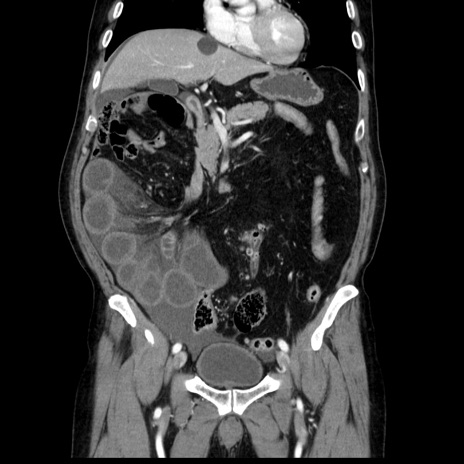

症例30(冠状断像)

【症例】80歳代男性

【主訴】臍周囲痛

【現病歴】約6時間前から臍下部痛が出現。次第に腹部膨隆・背部痛も生じてきたため来院。背部痛の場所は変化しない。

【身体所見】意識清明、BT 36.3℃、BP  131/87mmHg、P 87bpm、SpO2 100%(RA)、臍周囲自発痛・圧痛あり、反跳痛なし、自発痛部位に一致して板状硬あり、腹部膨隆、腸雑音減弱、CVA tenderness両側陰性。

【データ】WBC 19600、CRP 0.33